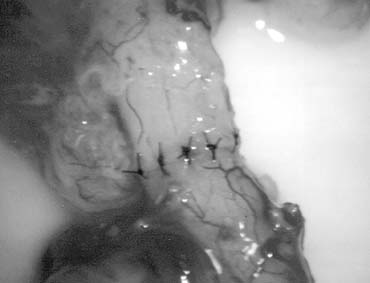

Testicular sperm extraction can result in injury to the testicular blood supply and lead to subsequent atrophy.70 The use of an operating microscope for standard open diagnostic testes biopsy allows identification of an area in the tunica albuginea free of blood vessels (Fig. 37), minimizing the risk of injury to testicular blood supply and allowing a relatively blood-free biopsy specimen.16 Using the microscope for testis biopsy, Schlegel15 discovered that in men with nonobstructive azoospermia, some of the tubules were larger than others. The larger tubules are more likely to yield sperm. Previous studies71 revealed that testicular biopsy in men with nonobstructive azoospermia display considerable heterogeneity. Examination of permanently fixed biopsy specimens that display heterogeneity reveal that tubules with spermatogenesis are of considerably larger diameter than tubules that are Sertoli cell-only (Figs. 38 and 39). This difference can be readably observed under the operating microscope.

Fig. 37. Microsurgical techniques allow clear identification of blood vessels on the tunica albuginia of the testis.

Fig. 38. Tubules with spermatogenesis are of larger diameter than tubules with Sertoli cell-only pattern.

Fig. 39. Selective removal of large seminiferous tubules with microsurgical testicular sperm extraction. A significantly smaller quantity of tissue is taken compared with conventional nonmicrosurgical testicular sperm extraction.